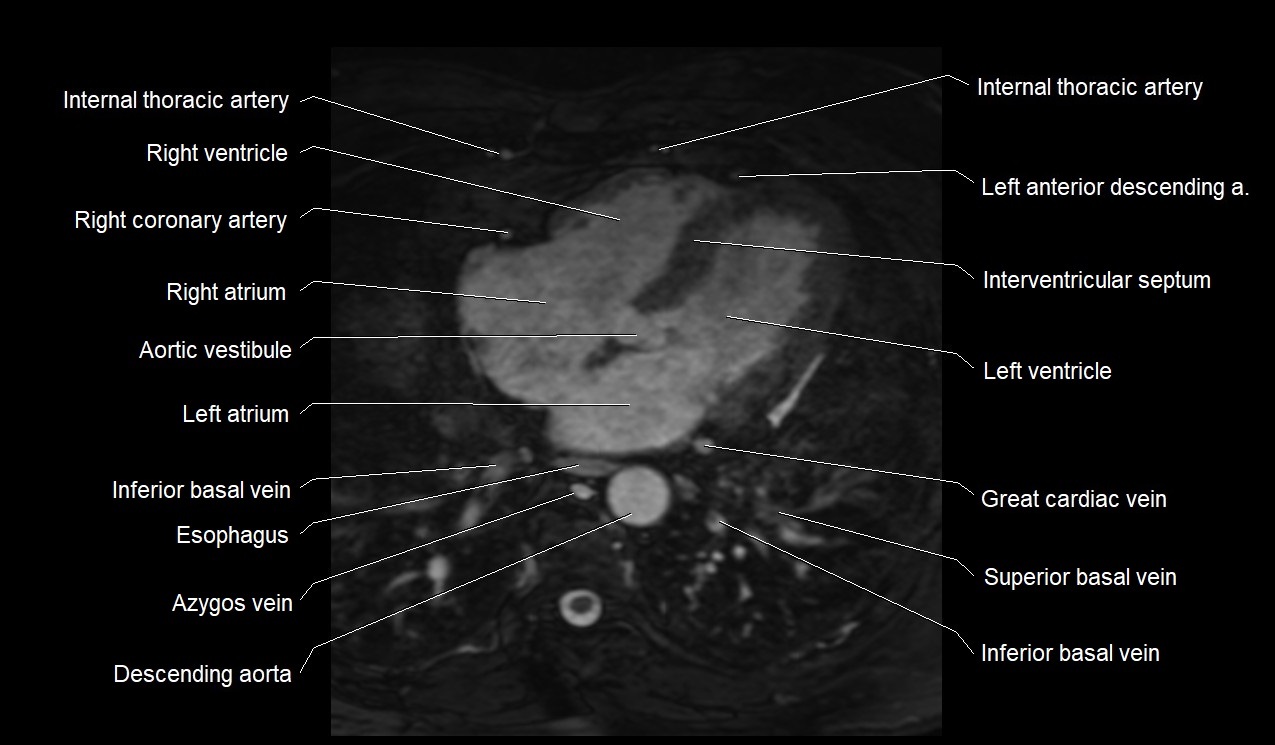

MRI image